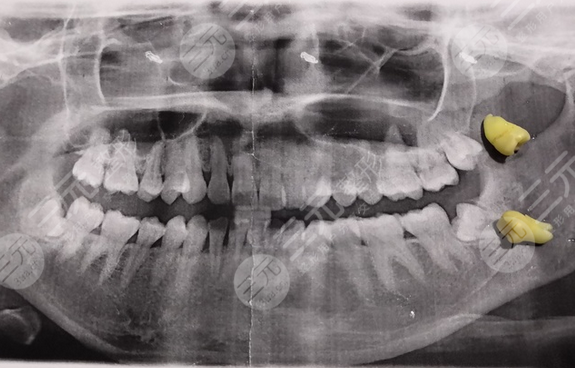

前段时间我才发现自己长了智齿,主要是因为我的智齿它开始发炎了,所以就不得不把它拔掉了,所以我就到了荆门雅泰口腔医院进行拔智齿手术,不过好在整个拔牙过程较为顺利,在拔牙前口腔医生先为我的牙齿进行检查,并拍了片,确定智齿的位置,以及拔除可能会存在的风险,根据我自身的情况,为我制定合理的方案,刚拔完牙的时候整个牙齿还好,但是过会的疼痛感就较为明X,并且整个脸也慢慢的肿了,第二天就肿得特别厉害,没有办法吃的食物有太多,现在已经是我拔完牙两周的时间了,整体恢复情况较为好,牙齿一点也不疼痛了,并且完全没有任何不适,十分感谢荆门雅泰口腔医院。